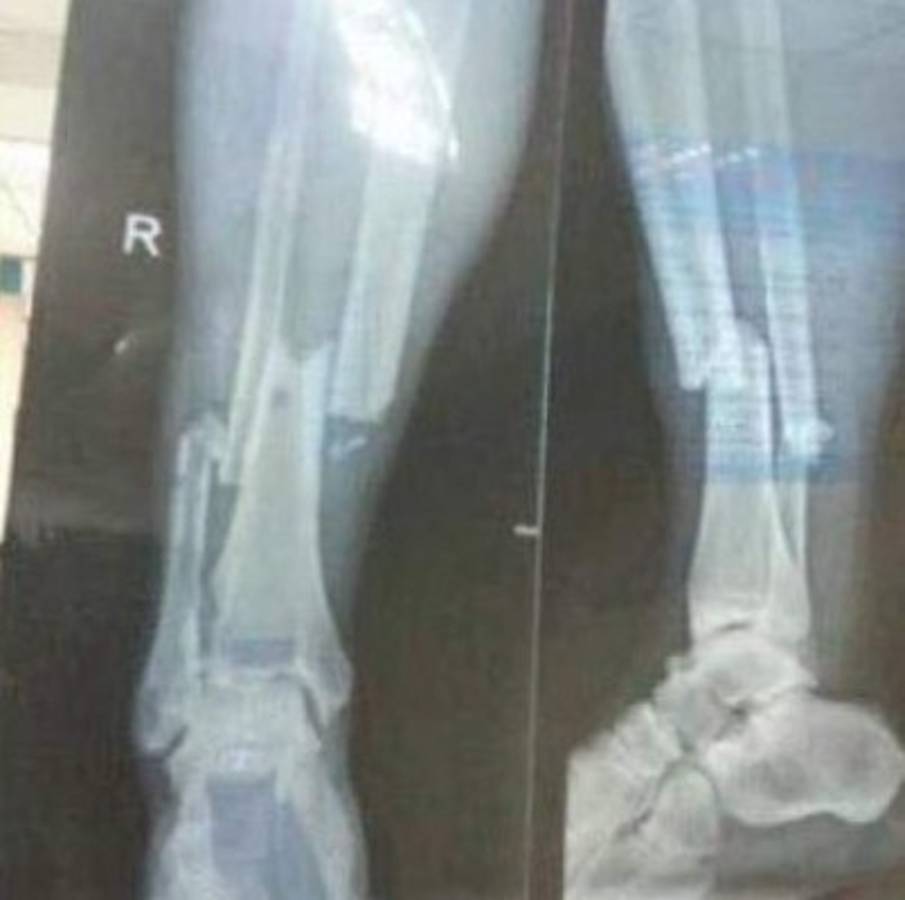

Este lunes hicieron los exámenes médicos a Demba Ba y la radiografía arroja esta terrible fractura.